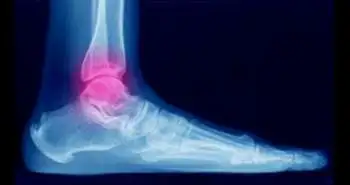

Bone density correlates with clinical outcomes after ankle fracture fixation

Osteoporosis and reduced bone density are associated with high fracture rate and severity.

Osteoporosis and reduced bone density are associated with high fracture rate and severity. The impact of bone density on fracture rate and related treatments are well known, but how the quality of bone influences the clinical results after fracture fixation is still unexplored. This study aimed to find this association.